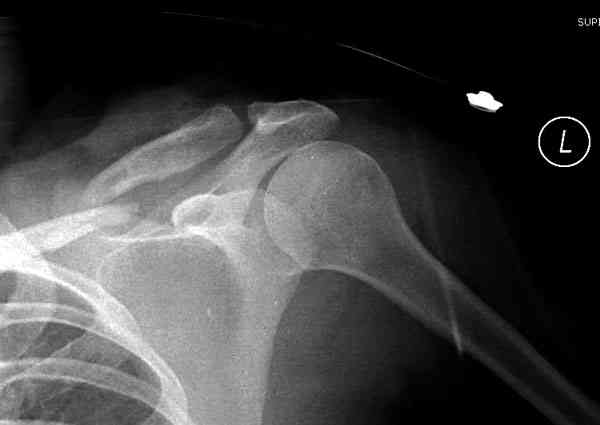

iГГШ> выполнения новокаиновой блокады дежурной бригадой выполнена закрытая

ГГШ> репозиция, наложены кольца Дельбе. Результаты репозиции показаны на

ГГШ> Результат стационарного лечения приведен на рентгенограмме (Xray_3).

Это картинка то есть через неделю после травмы, при выписке? Более чем приемлемо.